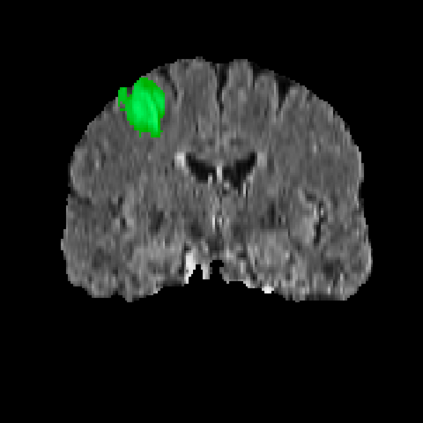

Automatic and accurate tumor segmentation on medical images is in high demand to assist physicians with diagnosis and treatment. However, it is difficult to obtain massive amounts of annotated training data required by the deep-learning models as the manual delineation process is often tedious and expertise required. Although self-supervised learning (SSL) scheme has been widely adopted to address this problem, most SSL methods focus only on global structure information, ignoring the key distinguishing features of tumor regions: local intensity variation and large size distribution. In this paper, we propose Scale-Aware Restoration (SAR), a SSL method for 3D tumor segmentation. Specifically, a novel proxy task, i.e. scale discrimination, is formulated to pre-train the 3D neural network combined with the self-restoration task. Thus, the pre-trained model learns multi-level local representations through multi-scale inputs. Moreover, an adversarial learning module is further introduced to learn modality invariant representations from multiple unlabeled source datasets. We demonstrate the effectiveness of our methods on two downstream tasks: i) Brain tumor segmentation, ii) Pancreas tumor segmentation. Compared with the state-of-the-art 3D SSL methods, our proposed approach can significantly improve the segmentation accuracy. Besides, we analyze its advantages from multiple perspectives such as data efficiency, performance, and convergence speed.

翻译:医疗图象上的自动和准确肿瘤分解是帮助医生诊断和治疗的高需求,然而,很难获得深学习模型所需的大量附加说明的培训数据,因为人工划定过程往往乏味,需要专门知识。尽管为解决这一问题,已经广泛采用了自我监督的学习(SSL)计划,但大多数SSL方法只侧重于全球结构信息,忽视肿瘤区域的主要特征:局部强度变化和大面积分布。本文提出SOSL(SAR),这是3D肿瘤分解的一种SSL方法。具体地说,设计了一个新的代用任务,即规模歧视,以预先将3D神经网络与自我重置任务结合起来。因此,预先培训的模型通过多尺度投入学习多层次的地方代表性。此外,还引入了一个对抗性学习模块,以学习多种无标签来源数据集的变异表达模式。我们展示了两种下游任务的方法的有效性:i)脑肿瘤分解、ii)Pancreas-剖析(SLA)的精度、3SL(SL)的精度分析方法,以及我们提议的SL(SL)的精度分析方法。